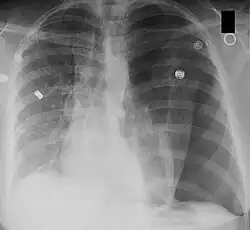

Ein Mediastinalshift oder eine Mediastinalverlagerung bezeichnet die Verschiebung des Mediastinums aus der Mittellinie des Thorax nach links oder rechts. Der Begriff wird in der Röntgendiagnostik verwendet.

Ursächlich ist entweder eine Verminderung des Volumens der Thoraxhälfte auf der Seite, zu der das Mediastinum verlagert ist, oder eine Vermehrung des Volumens auf der anderen Seite.